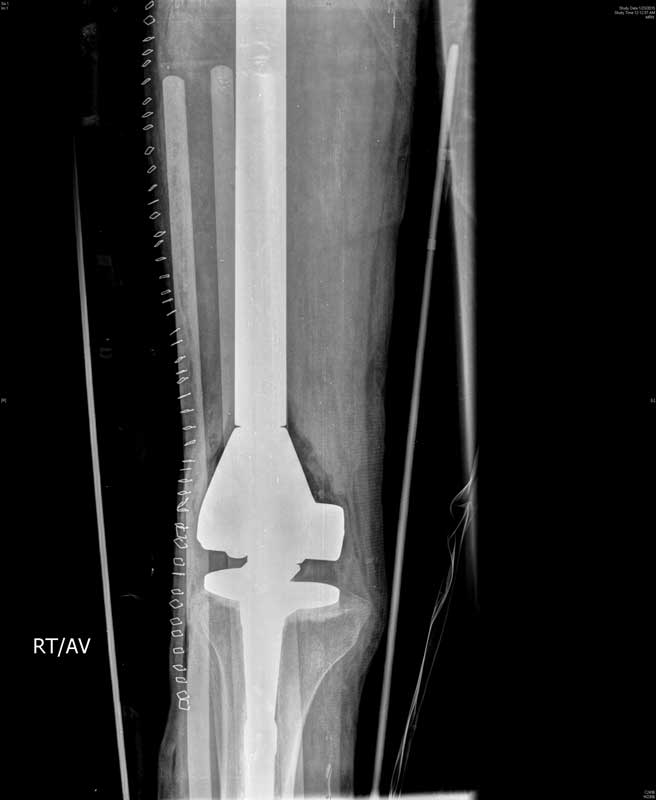

It is in New Delhi that the young Uzbek man got much needed medical succor. In a rare and difficult surgery that lasted 8 hours, Dr Rajeev K Sharma, Senior Consultant, Orthopedics & Joint Replacement Surgeon along with his team including Dr. V.P Singh, Cancer Surgeon at Indraprastha Apollo Hospitals, New Delhi, removed the entire cancer-affected bone right from the hip to the knee, replacing it with an artificial Total Femoral Replacement implant.

The difficult surgery which was a combination of Hip & Knee Replacement has successfully cured the patient of cancer, eliminating the risk of a permanent disability. A failure to get rid of the cancer affected bone would have lead to two eventualities: either a disarticulation of the hip (surgical removal of the entire lower limb at the hip level) or an amputation of the leg to save the life of the man. However, both these situations would have resulted in permanent disability.

“Total Femoral Replacement in this case was a very difficult and rare surgery as it was a kind of a combination of hip replacement, knee replacement and thigh bone replacement. To be able to get rid of the cancer completely, we needed to remove the entire stretch of thigh bone from the right hip to the right knee and reconstruct the same artificially. It was a challenging surgery as it involved the removal of whole thigh bone at the same time. The challenges included threat of post-surgical infection, knee and hip instability and damage to the nerves and vessels of the area. However, in an 8-hour procedure we successfully removed the full cancerous thigh bone and replaced it with an artificial Total Femoral Implant,” added Dr Sharma.